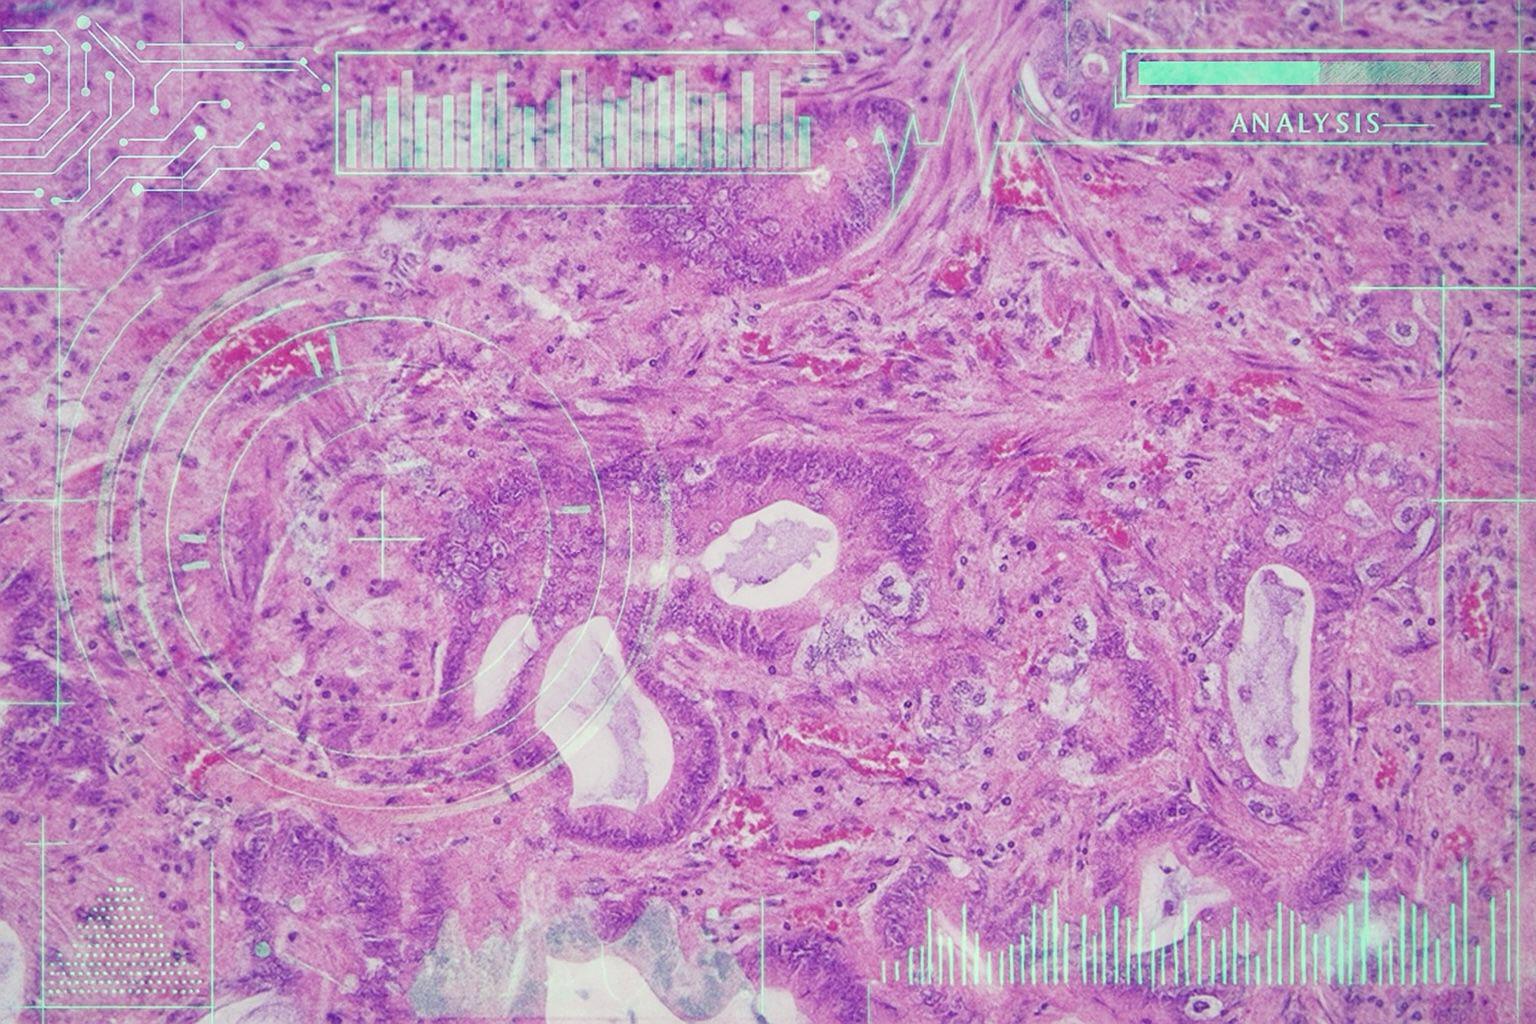

Come studenti di Ingegneria Biomedica e Medicine and Surgery – MedTech, ci siamo concentrati sull’ambito dell’Anatomia Patologica, che è il cuore della diagnosi, ma anche una delle unità operative più bisognosa di una rivoluzione digitale: se negli ambulatori e nelle sale chirurgiche i medici possono contare su monitor, ecografi, analisi e parametri in tempo reale, nell’Anatomia Patologica tutto dipende ancora dall’occhio umano, dalla sua capacità di leggere un vetrino e riconoscere nei tessuti segni di malattia. È proprio in questo contesto che l’intelligenza artificiale può cambiare le cose: confrontando migliaia di immagini in pochi istanti, diventa un alleato prezioso per il patologo, velocizzando diagnosi e prognosi e indirizzando i trattamenti. Algoritmi e calcolatori diventano dunque capaci di cambiare la vita dei pazienti, individuando pattern e indizi altrimenti invisibili.

È il caso del modello predittivo di DeepPathomics, un nuovo strumento in uso presso l’unità operativa di Anatomia Patologica del Policlinico Universitario Campus Bio-Medico di Roma, che mira a prevedere la risposta al trattamento nei pazienti con carcinoma polmonare non a piccola cellule in stadio III.

Nello studio “Deep Pathomics: A new image-based tool for predicting response to treatment in stage III non-small cell lung cancer” (Nibid et al., 2023) sono state impiegate reti neurali convoluzionali preaddestrate, tra cui GoogLeNet e ResNet, particolarmente efficaci nell’elaborazione di immagini, che hanno permesso di individuare nei tessuti microscopici architetture invisibili all’occhio umano.